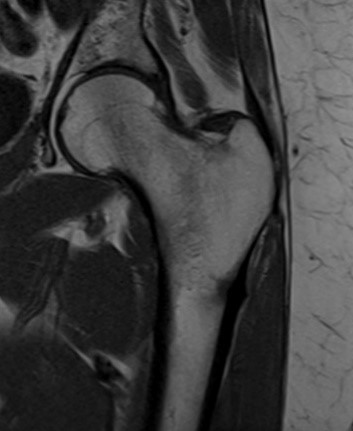

Considere que um paciente de 61 anos com dor no quadril após queda realizou exame para elucidação diagnóstica, demonstrado na imagem abaixo.

De acordo com a imagem, o exame realizado, o plano e a sequência são, respectivamente,